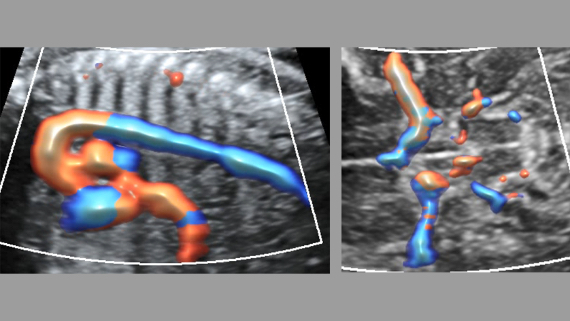

Immagini cliniche